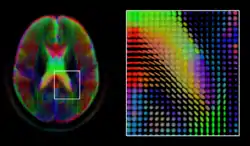

Diffusion MRI

Diffusion MRI is a structural magnetic resonance imaging modality that allows measurement of the diffusion process of molecules. Diffusion is measured by applying a gradient pulse to a magnetic field along a particular direction. In a typical acquisition, a set of uniformly distributed gradient directions is used to create a set of diffusion weighted volumes. In addition, an unweighted volume is acquired under the same magnetic field without application of a gradient pulse. As each acquisition is associated with multiple volumes, diffusion MRI has created a variety of unique challenges in medical image computing.

The diffusion tensor,[50] a 3 × 3 symmetric positive-definite matrix, offers a straightforward solution to both of these goals. It is proportional to the covariance matrix of a Normally distributed local diffusion profile and, thus, the dominant eigenvector of this matrix is the principal direction of local diffusion. Due to the simplicity of this model, a maximum likelihood estimate of the diffusion tensor can be found by simply solving a system of linear equations at each location independently. However, as the volume is assumed to contain contiguous tissue fibers, it may be preferable to estimate the volume of diffusion tensors in its entirety by imposing regularity conditions on the underlying field of tensors.[51] Scalar values can be extracted from the diffusion tensor, such as the fractional anisotropy, mean, axial and radial diffusivities, which indirectly measure tissue properties such as the dysmyelination of axonal fibers [52] or the presence of edema.[53] Standard scalar image computing methods, such as registration and segmentation, can be applied directly to volumes of such scalar values. However, to fully exploit the information in the diffusion tensor, these methods have been adapted to account for tensor valued volumes when performing registration [54][55] and segmentation.[56][57]

Given the principal direction of diffusion at each location in the volume, it is possible to estimate the global pathways of diffusion through a process known as tractography.[58] However, due to the relatively low resolution of diffusion MRI, many of these pathways may cross, kiss or fan at a single location. In this situation, the single principal direction of the diffusion tensor is not an appropriate model for the local diffusion distribution. The most common solution to this problem is to estimate multiple directions of local diffusion using more complex models. These include mixtures of diffusion tensors,[59] Q-ball imaging,[60] diffusion spectrum imaging [61] and fiber orientation distribution functions,[62][63] which typically require HARDI acquisition with a large number of gradient directions. As with the diffusion tensor, volumes valued with these complex models require special treatment when applying image computing methods, such as registration [64][65][66] and segmentation.[67]